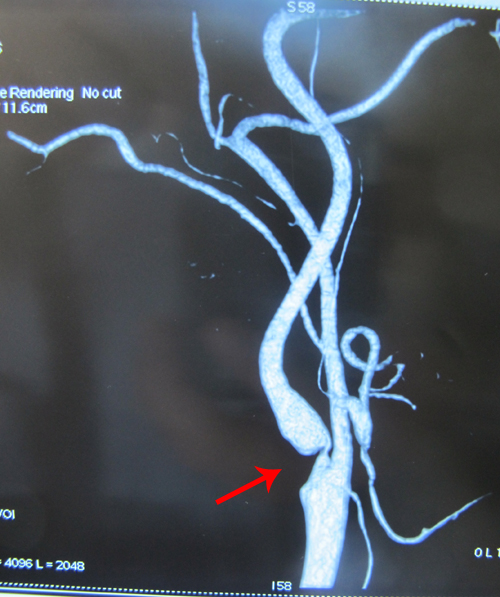

脑血管造影(2011-3-9):头臂干、左颈总动脉、左锁骨下动脉开口未见异常。左侧颈内动脉起始部狭窄,最狭窄处约90%。造影剂呈细线样通过,边缘尚光滑,颅内各级分支血管分布均匀,未见血管畸形、动脉瘤及血管狭窄等异常征象。左椎动脉造影有大脑后动脉未见显影,基底动脉显示良好,左侧大脑前、大脑中动脉显影。右颈内动脉显示良好,右颈内动脉造影见后交通动脉显示良好,右大脑后动脉显示良好,未见明显狭窄、动脉瘤、动静脉畸形等异常征象,也未见占位征象。右椎动脉造影见基底动脉未显影,只显示右侧小脑后下动脉,其余均未显示

左侧颈内动脉重度狭窄

该患者为老年男性,主要表现为反复发作头晕, DSA示其左侧颈内动脉起始部狭窄,最狭窄处约90%。另外,患者有“血脂高、肺气肿”病史,为脑卒中高危人群。实施颈动脉内膜剥脱术可有效预防其发作卒中。